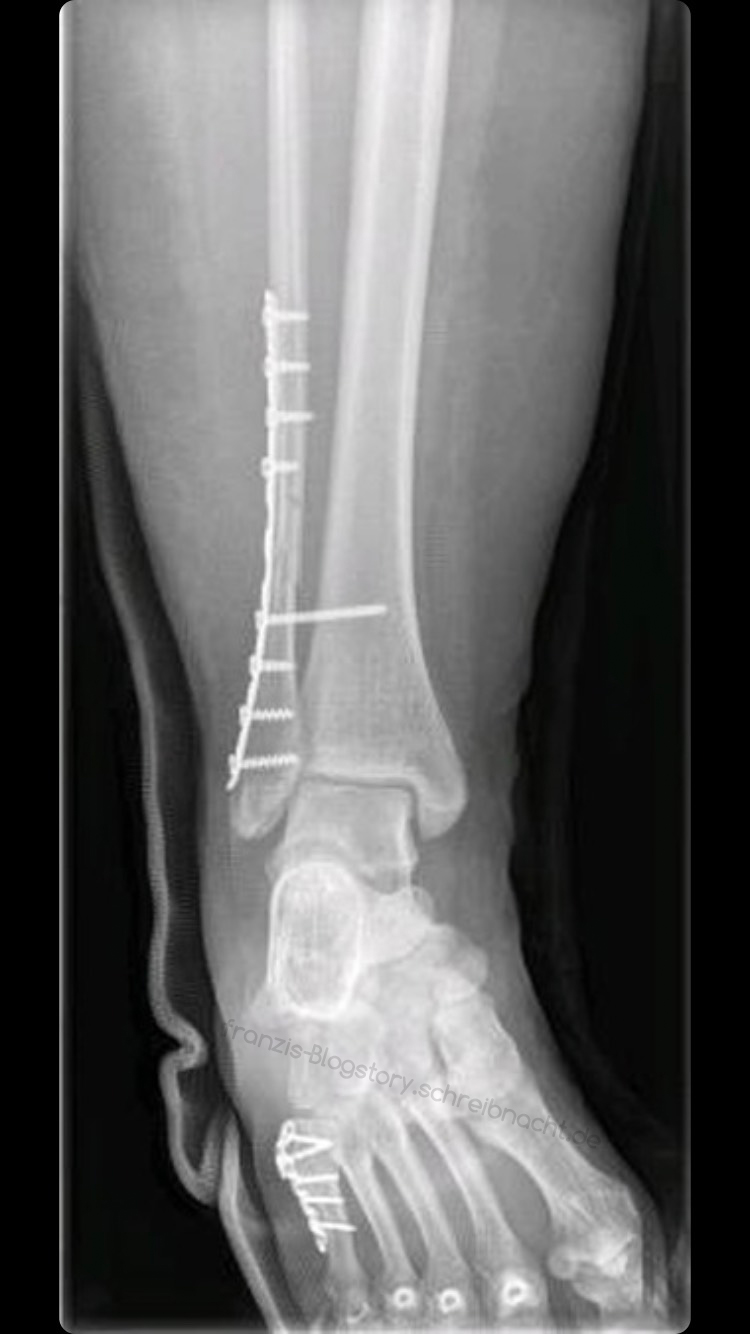

Source: thestrixylw.pages.dev Das Sprunggelenk Anatomie und Chirurgie OTA Franzi , Entfernung von Drähten, Schrauben und Platten nach Osteosynthese - Dauer, Genesung und mehr Eine mögliche Ursache für Fußschmerzen sind Schrauben, die im Rahmen einer Osteosynthese eingesetzt wurden

Source: nologeotw.pages.dev Wände einziehen durch Trockenbau HORNBACH Luxemburg , Wann Platte entfernen? Wann können die Schrauben und Platten frühestens entfernt werden? Eine Metallentfernung kann frühestens bei gesicherter Knochenheilung, was meistens nach 6 Wochen bereits der Fall ist, erfolgen Einige Patienten berichten auch von wetterbedingten Schmerzen im Fuss oder Knöchel.

Source: mitthjemika.pages.dev Fuß gebrochen Unfallchirurgie Bad Soden / Frankfurt , Allerdings kann das Metall im Körper gesundheitliche Risiken wie eine stärkere Neigung zu Knochenbrüchen oder Infektionen begünstigen Bei einigen Patienten kann das Osteosynthesematerial jedoch hervortreten oder eine nahegelegene Sehne oder andere Weichteile reizen